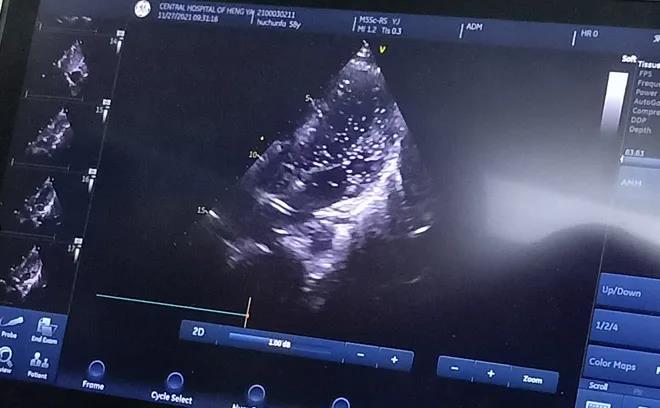

經(jīng)充分的術(shù)前準(zhǔn)備后, 11月27日上午,胡先生接受局部麻醉下經(jīng)皮介入PFO封堵術(shù),手術(shù)全程病人清醒,醫(yī)生一邊與胡先生交流,一邊進(jìn)行手術(shù),術(shù)后無傷口創(chuàng)面?;颊弋?dāng)天即下床活動(dòng),復(fù)查心臟彩超提示封堵器位置良好。

胸超聲心動(dòng)圖引導(dǎo)下經(jīng)股靜脈房間隔缺損封堵術(shù)是在胸超聲心動(dòng)圖實(shí)時(shí)監(jiān)測(cè)下的封堵術(shù),與傳統(tǒng)開胸行房間隔缺損修補(bǔ)術(shù)相比,只需要通過大腿股靜脈進(jìn)行穿刺便可完成,出血少、不縫針,真正做到了“微創(chuàng)”,創(chuàng)傷小且不影響美觀;與內(nèi)科介入下手術(shù)相比,又避免了X線對(duì)患者的放射損傷。在胸超聲實(shí)時(shí)引導(dǎo)下操作,定位準(zhǔn)確,隨時(shí)可調(diào)整封堵傘位置,適合于繼發(fā)孔房間隔缺損、室間隔缺損、動(dòng)脈導(dǎo)管未閉等各種常見先天性心臟病的治療,對(duì)先心病心臟病患者的治療又提供了一項(xiàng)新的微創(chuàng)治療方法。該技術(shù)因創(chuàng)傷小、恢復(fù)快,術(shù)后3至5天即可出院。